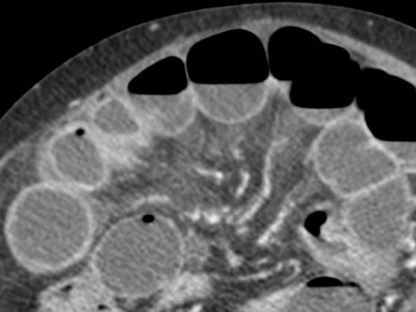

Se realiza TC de abdomen en vacío y con contraste en fase portal:

Estamos ante un cuadro de isquemia intestinal en un paciente con bajo gasto cardiaco con afectación principal de asas intestino delgado, territorio vacularizado por la arteria mesentérica superior.

Flecha roja: colateral que repermeabiliza la AMS.